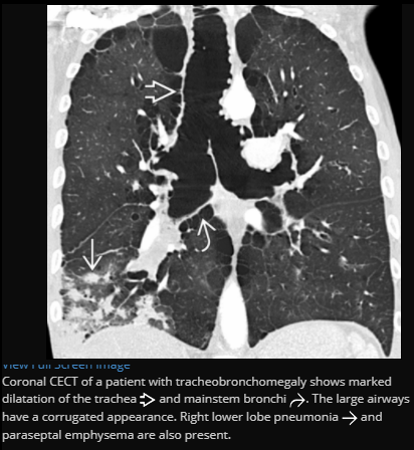

Tracheobronchomegaly (Mounier-Kuhn syndrome)

Dilatation of trachea & central bronchi that impairs ability to clear mucus

Tracheobronchomegaly; Mounier-Kuhn syndrome

Coronal CECT of a patient with tracheobronchomegaly shows marked dilatation of the trachea (open arrow) and mainstem bronchi . The large airways have a corrugated appearance. Right lower lobe pneumonia (straight arrow) and paraseptal emphysema are also present.